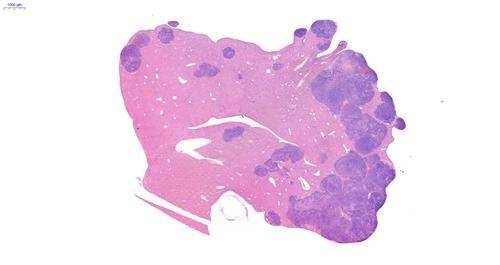

2、Hepa1-6肝原位瘤肝脏HE染色图

image.png